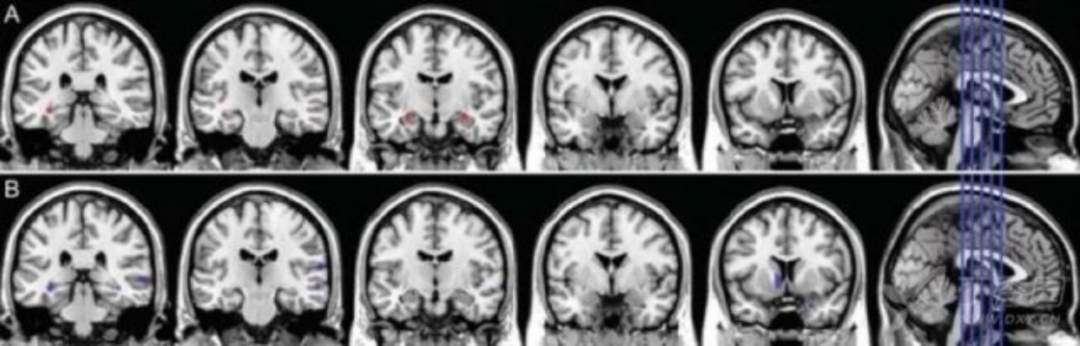

3.结构磁共振(sMRI) sMRI 可测量区域性或全脑体积大小,反映因细胞损伤、轴突退变、突触失调引起的结构萎缩。最早出现并进行性加重的内侧颞叶结构萎缩可能是 AD 早期出现的特征性改变,其中海马萎缩,被认为是 MCI 进展到 AD 痴呆的最佳标志物。研究还发现,AD 早期人群的皮层灰质、内嗅皮层和海马旁回也存在萎缩。MCI 患者可出现皮质厚度变薄和全脑体积变小,可用于预测 MCI 向 AD 的转化。2011 年 NIA-AA 诊断标准将 sMRI 作为 AD 神经损伤标记物之一;然而 2014 年最新的 IWG-2 标准认为 sMRI 可能更适合用于测量和监测疾病过程。

图 4 正常对照组(CN)、aMCI 和 AD 患者的海马体积结构 MRI 成像